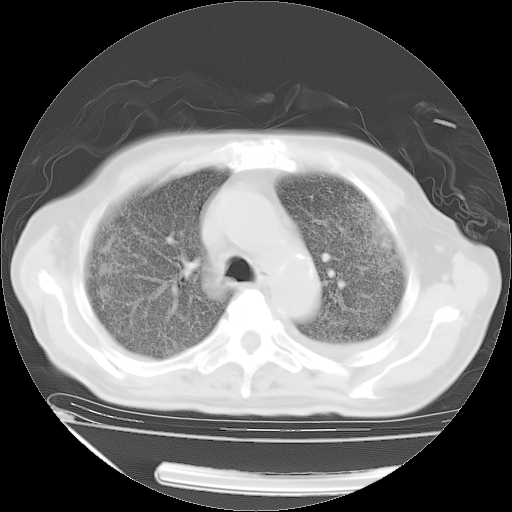

仔细阅读病史资料和CT,我觉得两肺粟粒结核要高度怀疑。

昨天我们影像科主任说由于12天前在齐鲁医院的肺部CT无确切改变,所以不考虑肺结核。

但我们感染病科老主任认为粟粒性肺结核可能性大。

今天带四次肺CT片到市医院,影像科4~5个主任都认为不考虑粟粒性肺结核。主要理由是在3月19日、4月2日、4月27日的CT片没有见到确切异常(肺结核)影像。影像科主任们建议找呼吸内科主任,呼吸内科主任认为首先考虑粟粒性肺结核。

甲强龙80mg/日+抗结核治疗(异烟肼+利福霉素+乙胺丁醇)10天。复查肺部CT。

治疗10天肺部CT